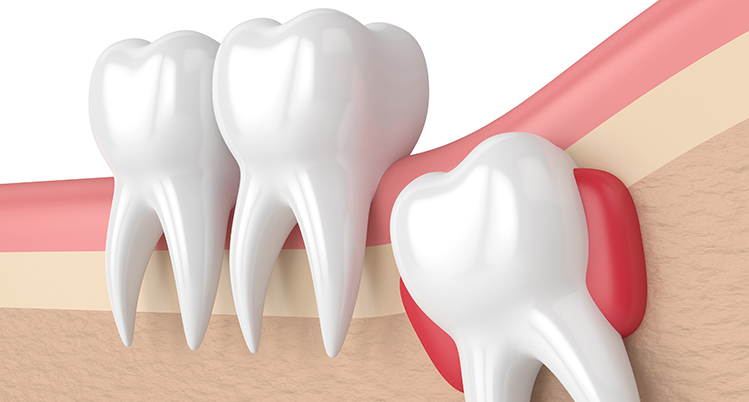

親知らずとは

痛みの原因

頭が少しだけでている状態の時は磨くのが難しいため、汚れが溜まって歯茎が腫れ痛みがでることがあります。

疲れなどで免疫力が下がると症状がでやすくなります。